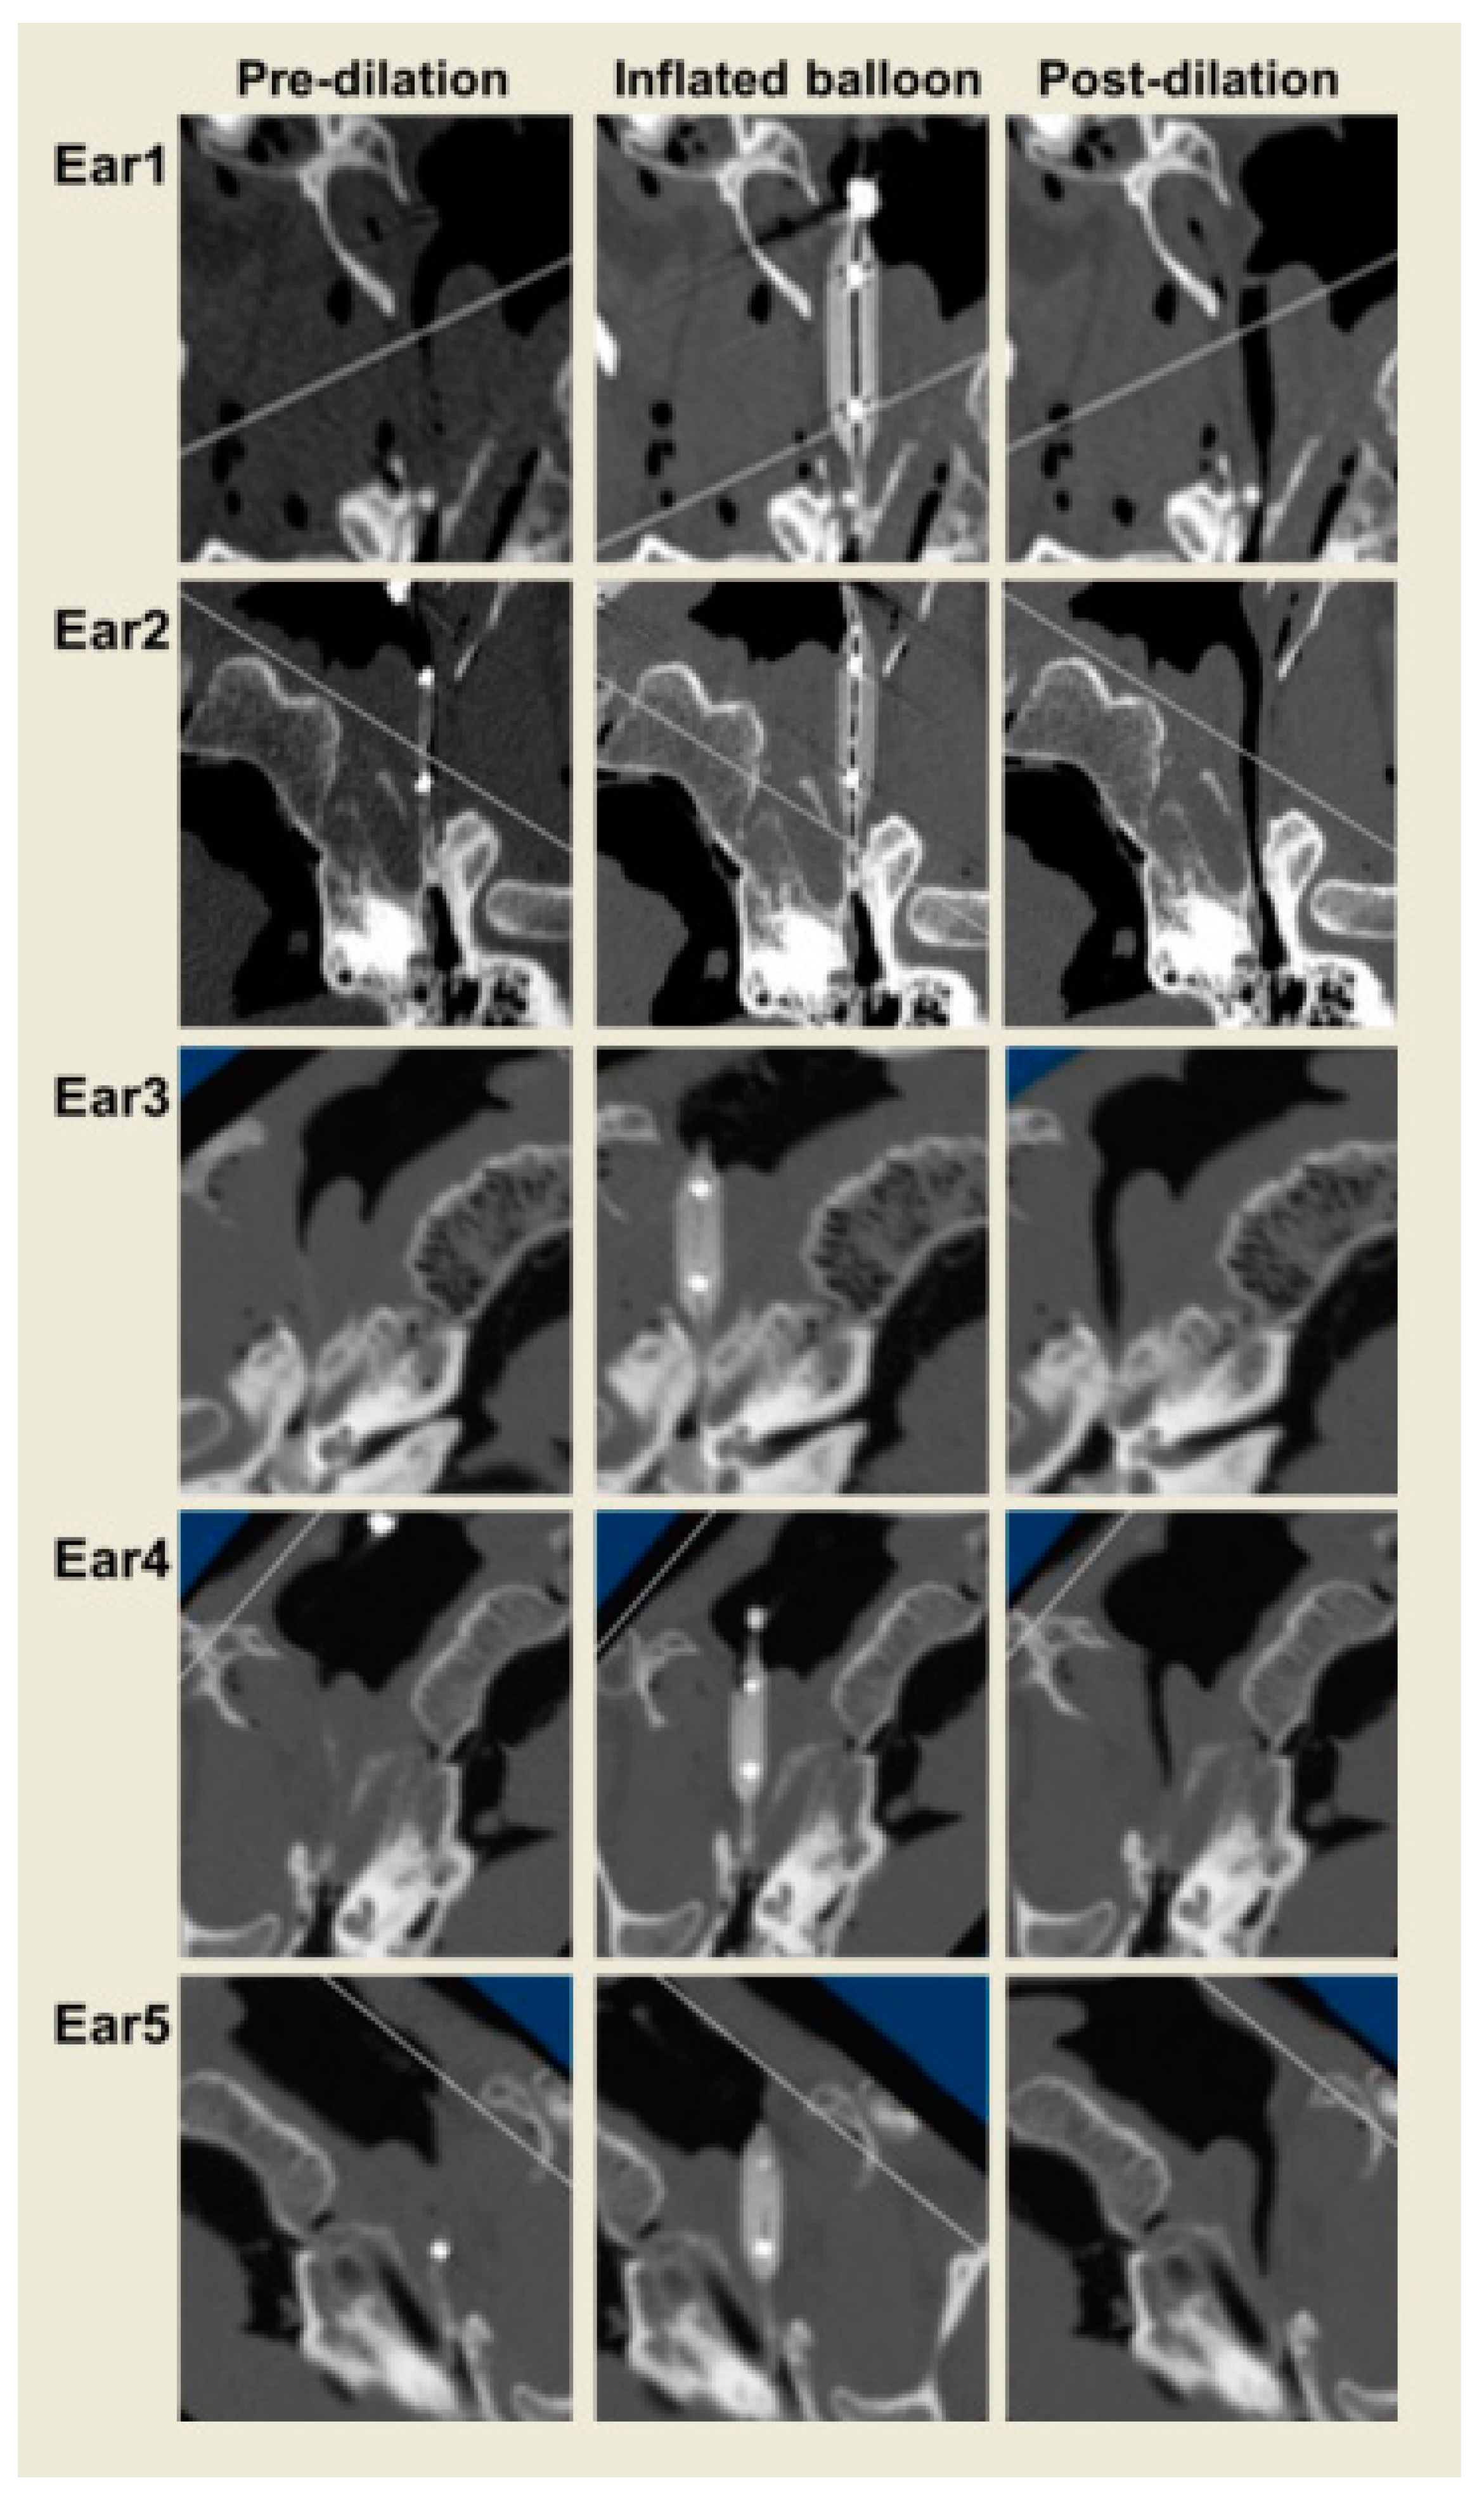

3. Results

| Small | Longest | Long | |

|---|---|---|---|

| Ear 1 | 20 | 6 | 8 |

| Ear 2 | 33 | 23 | 26 |

| Ear 3 | 68 | 50 | 62 |

| Ear 4 | 100 | 74 | 97 |

| Ear 5 | 98 | 68 | 88 |

| % Increase | 64 | 44 | 56 |